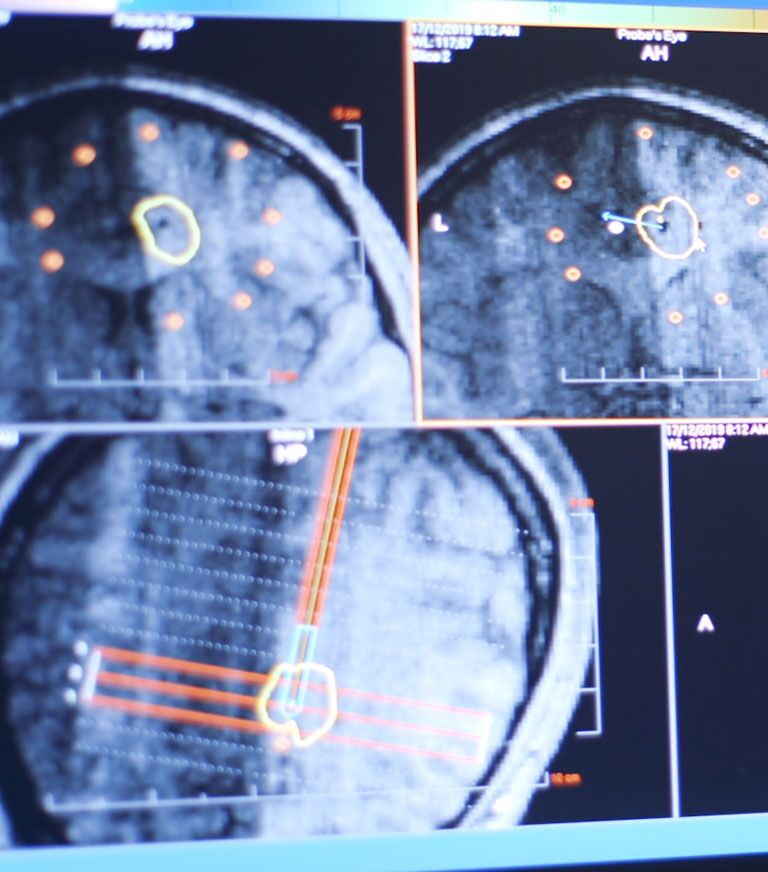

• Our operating rooms feature top navigation systems including FIREFLY and StealthStation S8 with 3D visualization, allowing surgeons to perform safer, more precise procedures.

• Minimally invasive surgery tools including MRI-guided laser ablation and ROSA, a 3D-mapping robotic system that aids surgeons in locating the exact area to operate.